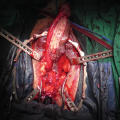

Free Flap Urethroplasty

Free flap urethral reconstruction was originally described in oncological cases, but also as salvage option after partial necrosis of the neourethral part of a tube-in-tube phalloplasty, or in patients who are not eligible for a tube-in-a-tube RFFF or ALT phalloplasty, but who do wish to void in the standing position. The use of the RFFF, gracilis flap, ulnar flap and pedicled superficial circumflex iliac artery perforator flap (SCIPF) are described for urethral reconstruction [27, 31, 32]. The RFFF is a superior flap, with thin skin and a long vascular pedicle, which makes is suitable for urethral reconstruction and microsurgical vascular anastomosis in the groin. It provides the most effective single-stage urethral reconstruction, without the distinctive scar in the forearm. The disadvantage is that it requires a complex, microvascular surgery, performed together with a pedicled perforator flap. A rectangular RFFF of approximately 3 × 16 cm is designed and harvested from the non-dominant forearm. Donor site is closed primarily or covered with a split-thickness skin graft. The vascular pedicle is carefully dissected from the distal to the proximal end, to its origin at the brachial artery. The flap is tubularized in two layers around an 18 Fr Foley catheter with the skin facing the catheter. Labia minora flaps are created on both sides, and conjoined over a catheter to lengthen the native urethra. After elevation of the RFFF and pedicle dissection, the flap is transferred to the genital region. First, the urethral anastomosis with previously formed bulbar part is performed in a two-layer fashion. The vascular pedicle is tunneled to the groin, the radial artery is anastomosed to the common femoral artery and the cephalic vein to the great saphenous vein. In this way, complete urethral lengthening is performed as a single-stage procedure. However, long-term urethral complications are reported in more then 50% of cases, including urethral stricture, fistula and hairy urethra. Also, microsurgical anastomosis carries a risk of vascular accidents and flap loss [27, 32].